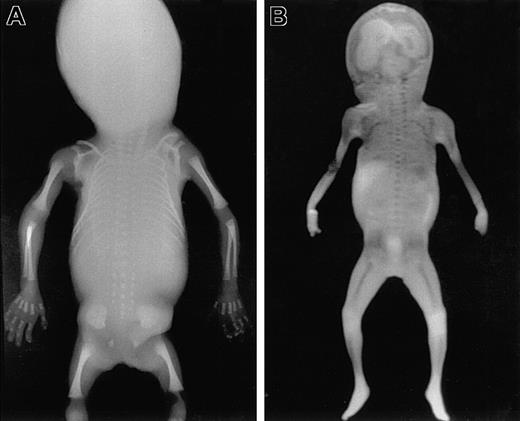

To identify areas of BM in the fetal skeleton, total body radiography of fetuses of different gestational ages was performed (Figure 1A) showing ossification centers in the skull, spine, claviculae, scapulae, costae, humeri, ulnae, radius, pelvis, femora, tibiae, fibula, and the bones of the hands and feet. Corresponding sites could be visualized using MRI (Figure 1B). All sites except the skull were confirmed to contain hematopoietic cells by microscopic histologic analysis (Figure2). In the skull, only the mandibula, maxilla, clivus (a bony surface in the posterior fossa), and occipital bones contained hematopoietic cells during the gestational ages studied. The other skull bones showed bone formation but no marrow containing hematopoietic cells and were therefore excluded from calculation of the BM compartment. The hematopoietic sites confirmed by histologic analysis correlated well with the BM areas found on the MRI (Figure 3), and thus the volume of these hematopoietic sites could be determined from the MRIs.

Total body radiography and coronal MRI.

Total body anteroposterior radiograph image (A) and T1-weighted coronal scout MRI (B) of a fetus 21 weeks of gestational age. Areas of ossification containing BM are clearly recognizable as radiodense structures in the radiograph. Corresponding areas of low signal intensity (dark) are visible in the MRI. These areas are well delineated from the surrounding cartilage, which shows much higher signal intensity (light).